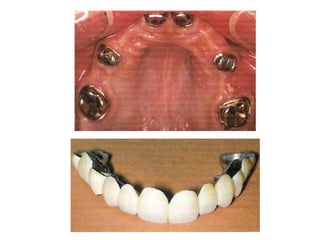

* Implant supported fixed

prosthesis: are surgically placed

implant within bone and projected

though the mucosa, on which the

abutment are screw retained , fixed

partial denture the constructed on

the abutment

* Implant supportedfixed prosthesis: are surgically placed implant within bone and projected though the mucosa, on which the abutment are screw retained , fixed partial denture the constructed on the abutment